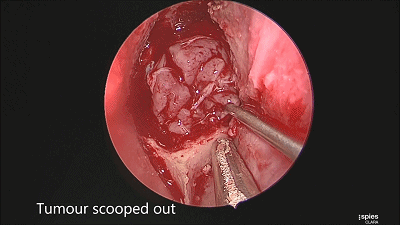

▼刮匙轻轻刮取肿瘤。

▼留取肿瘤标本。

▼本例垂体腺瘤质软,易于吸除。

▼继续仔细吸除瘤腔死角的肿瘤。